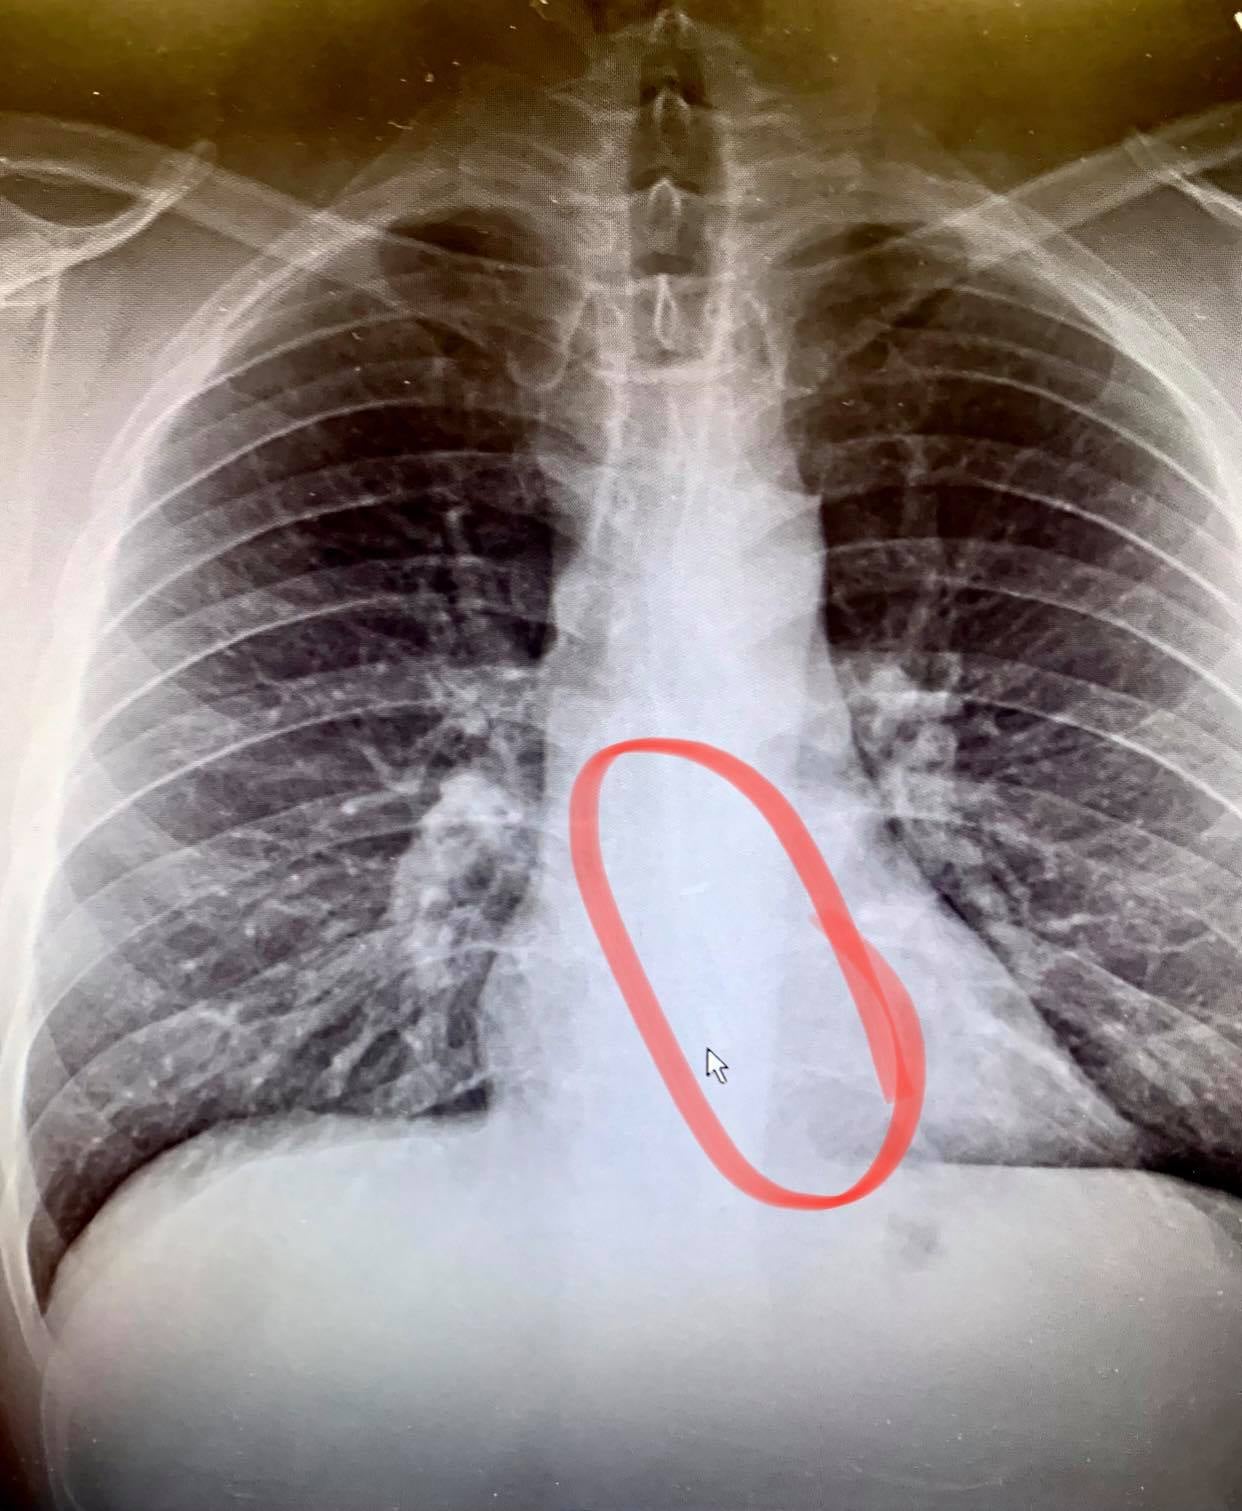

Carli Bellmer, que responde al nombre de @IamCarliiib, dijo a sus seguidores que finalmente se tragó el AirPod, lo que fue confirmado por una radiografía. Pero antes de que el auricular saliera de su cuerpo, Bellmer cuenta que envió a su amiga una nota de voz que el AirPod, extrañamente, transmitió de forma audible desde el interior de su estómago.

La TikToker también aseguró a sus seguidores que una radiografía mostró que el AirPod ya no estaba en su estómago. “Una radiografía mostró que lo pasé. Tenía la sensación de que lo había pasado. No lo encontré, pero sé que lo he pasado. Sé que estaba en mi estómago y que ya no está”, dijo.